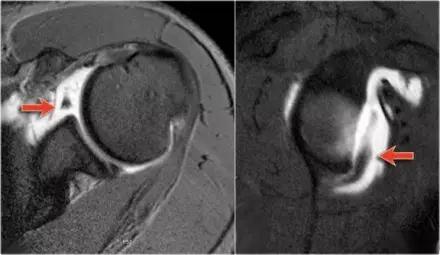

2. Bankart 损伤(Bankart lesion)

是指盂唇前下方在前下盂肱韧带复合体附着处的撕脱性损伤,是肩关节复发性前脱位最常见的原因和最重要的病理基础。

Bankart 损伤(来源:Radiology assistant)

Bankart 损伤的 MR 片 (来源:Radiology assistant)

3. 骨性 Bankart 损伤(Bony Bankart lesion)

下盂肱韧带盂唇复合体损伤同时伴有关节盂前下方的撕脱性骨折。由于关节盂前下方的骨质缺损,可以导致梨形的肩盂变为「倒梨形」结构,出现关节不稳的主要因素。

骨性 Bankart 损伤的 MR(左)和 CT(右)(来源:ShoulderDoc)

骨性 Bankart 损伤的 MR(左)和关节镜图(右)(来源:ShoulderDoc)